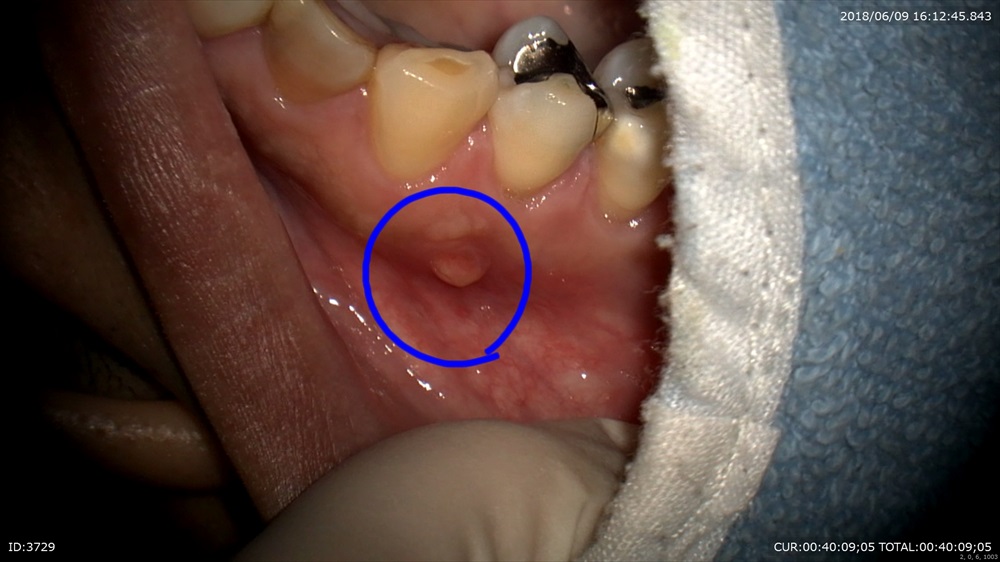

「歯茎の腫れが治らない。様子を見ましょうといわれ不安」

こんなに腫れています。

このようなケースだから初診で削りません。

この腫れができる原因は

①根尖性周囲炎

②歯周病

③歯根ハセツ

④口内炎

など沢山あります。これを直ぐに診ただけでは断定できす、あらゆる可能性を疑い根本的な解決を探します。しかも外傷が引き金の場合かみ合わせの調整も必要。ここで直ぐに削ると原因が見えなくなります。だから「精密検査」の後に患者さまと治療の選択肢をお話し、歯科医師主導ではなく一緒に考えていくシステムをとっています。